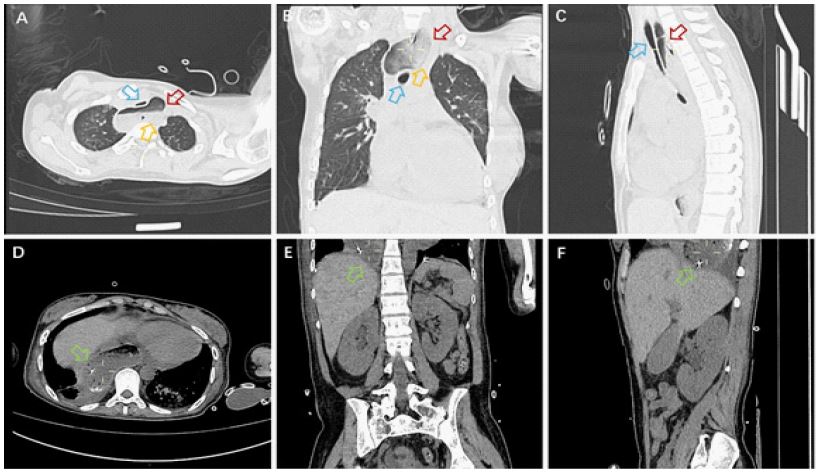

A 24-year-old female was admitted to the hospital due to muscle soreness in the limbs, retrosternal pain, and difficulty swallowing for over 50 days. Upon admission, physical examination revealed proximal muscle strength of level 3 in both upper limbs and level 5 in distal muscles, proximal muscle strength of level 4 in both lower limbs and level 5 in distal muscles, with no muscle atrophy or pseudohypertrophy observed, and normal muscle tone. Laboratory tests indicated that creatine kinase 4474 U/L, lactate dehydrogenase 330 U/L, interleukin-6 266.94 pg/ml, erythrocyte sedimentation rate 38 mm/h. The idiopathic inflammatory myopathy profile revealed a nucleolar-pattern Antinuclear Antibody (ANA) titer of 1:100 and strongly positive anti-NXP2 IgG antibodies (+++). Electromyography suggested possible myogenic damage, and chest CT indicated dilation of the upper esophagus with contents, measuring up to 5.6 centimeters at its widest point. Abdominal CT showed a gas-containing stomach sac above the diaphragm, suggesting a hiatal hernia (Figure 1). The patient was diagnosed with dermatomyositis, considering the esophageal dilation and hiatal hernia as manifestations of dermatomyositis in the digestive tract. After treatment with prednisone, methotrexate, and tocilizumab, the patient’s symptoms gradually improved.

Figure 1: Imaging of the esophageal dilation. (A-C) Esophageal dilation; (D-F) Esophageal hiatus hernia. Blue arrow: Trachea; Red arrow: Esophagus; Orange arrow: Contents of the esophagus; Green arrow: Esophageal hiatal hernia.